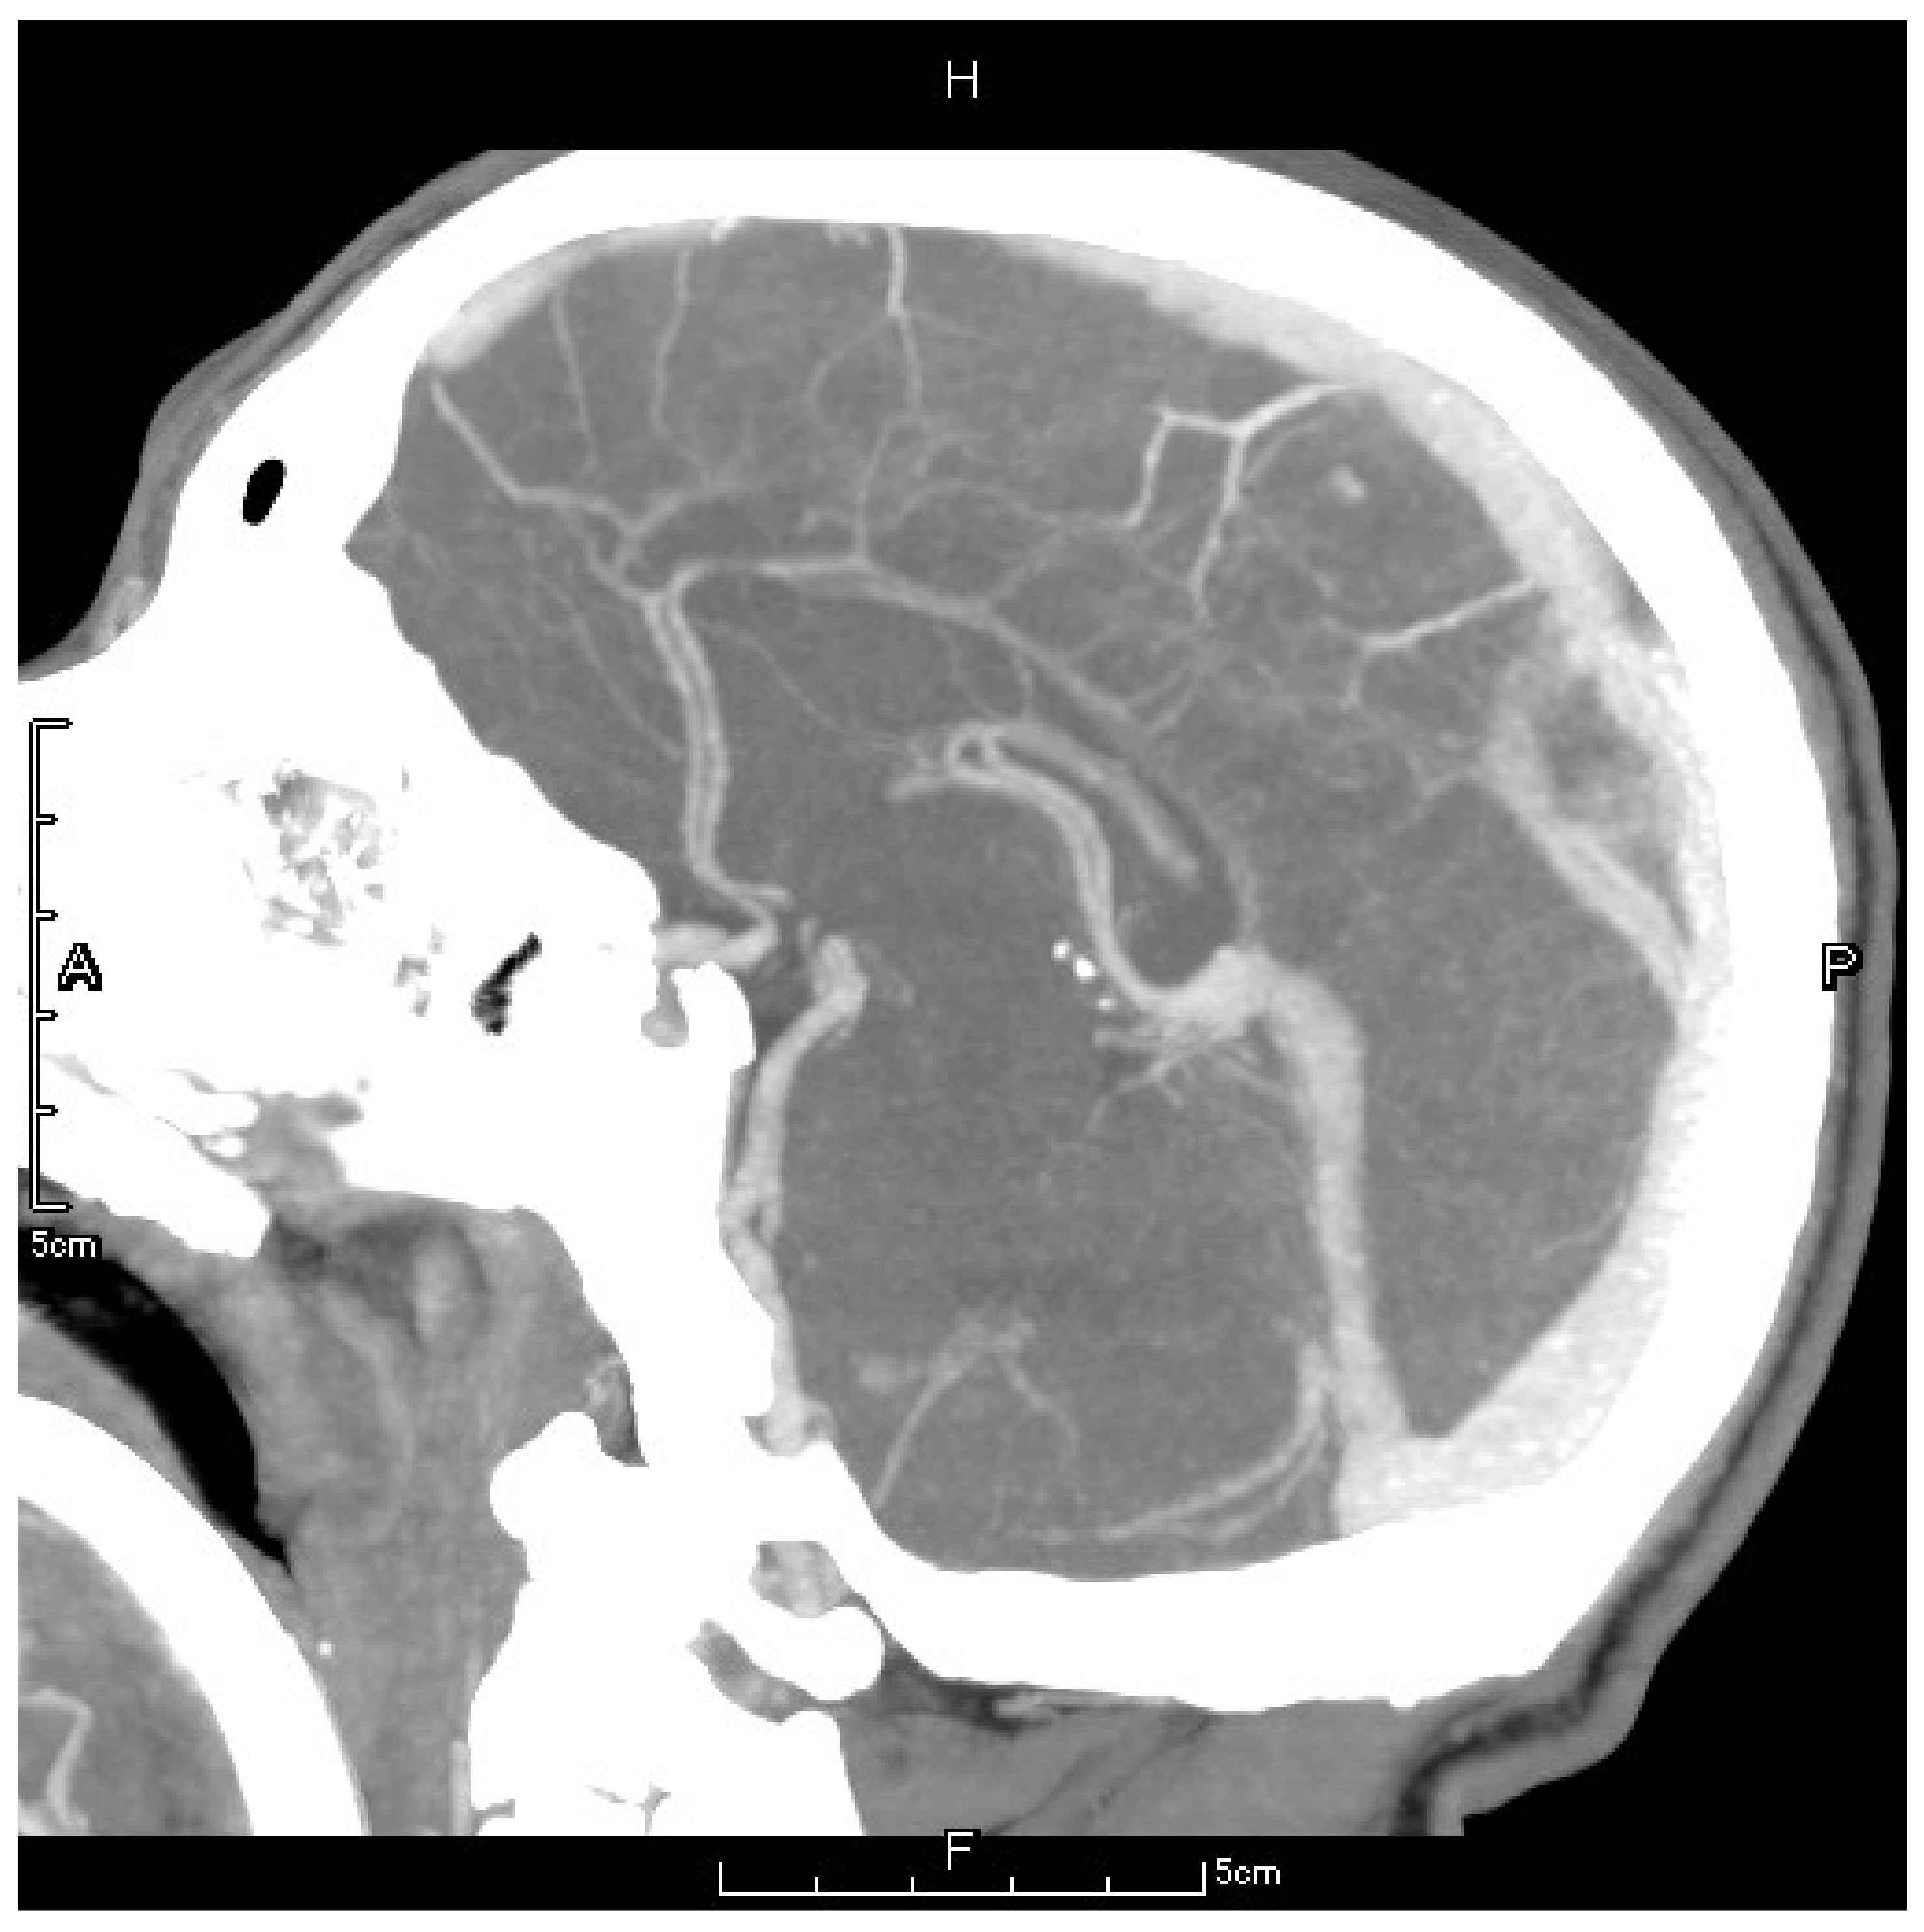

2. Case Presentation

2.4. Postoperative Management